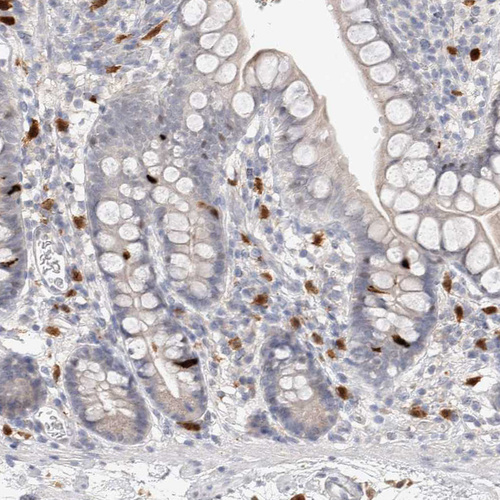

Immunohistochemical staining of human bone marrow shows moderate cytoplasmic positivity in megakaryocytes.